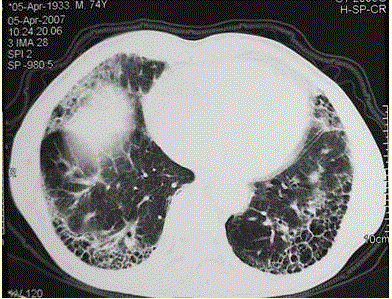

问题  患者男,73岁。进行性呼吸困难半年,加重2个月。否认吸烟史、粉尘接触史。查体:发绀,杵状指,双肺底闻爆裂音。血常规正常,ERS 16 mm/h。胸部CT 如图所示。 对该患者进行下一步的检查中,应首选

选项 A、6 min步行试验 B、支气管镜检查 C、肺功能检查,包括通气及弥散功能检查 D、血气分析 E、开胸肺活检

答案 B